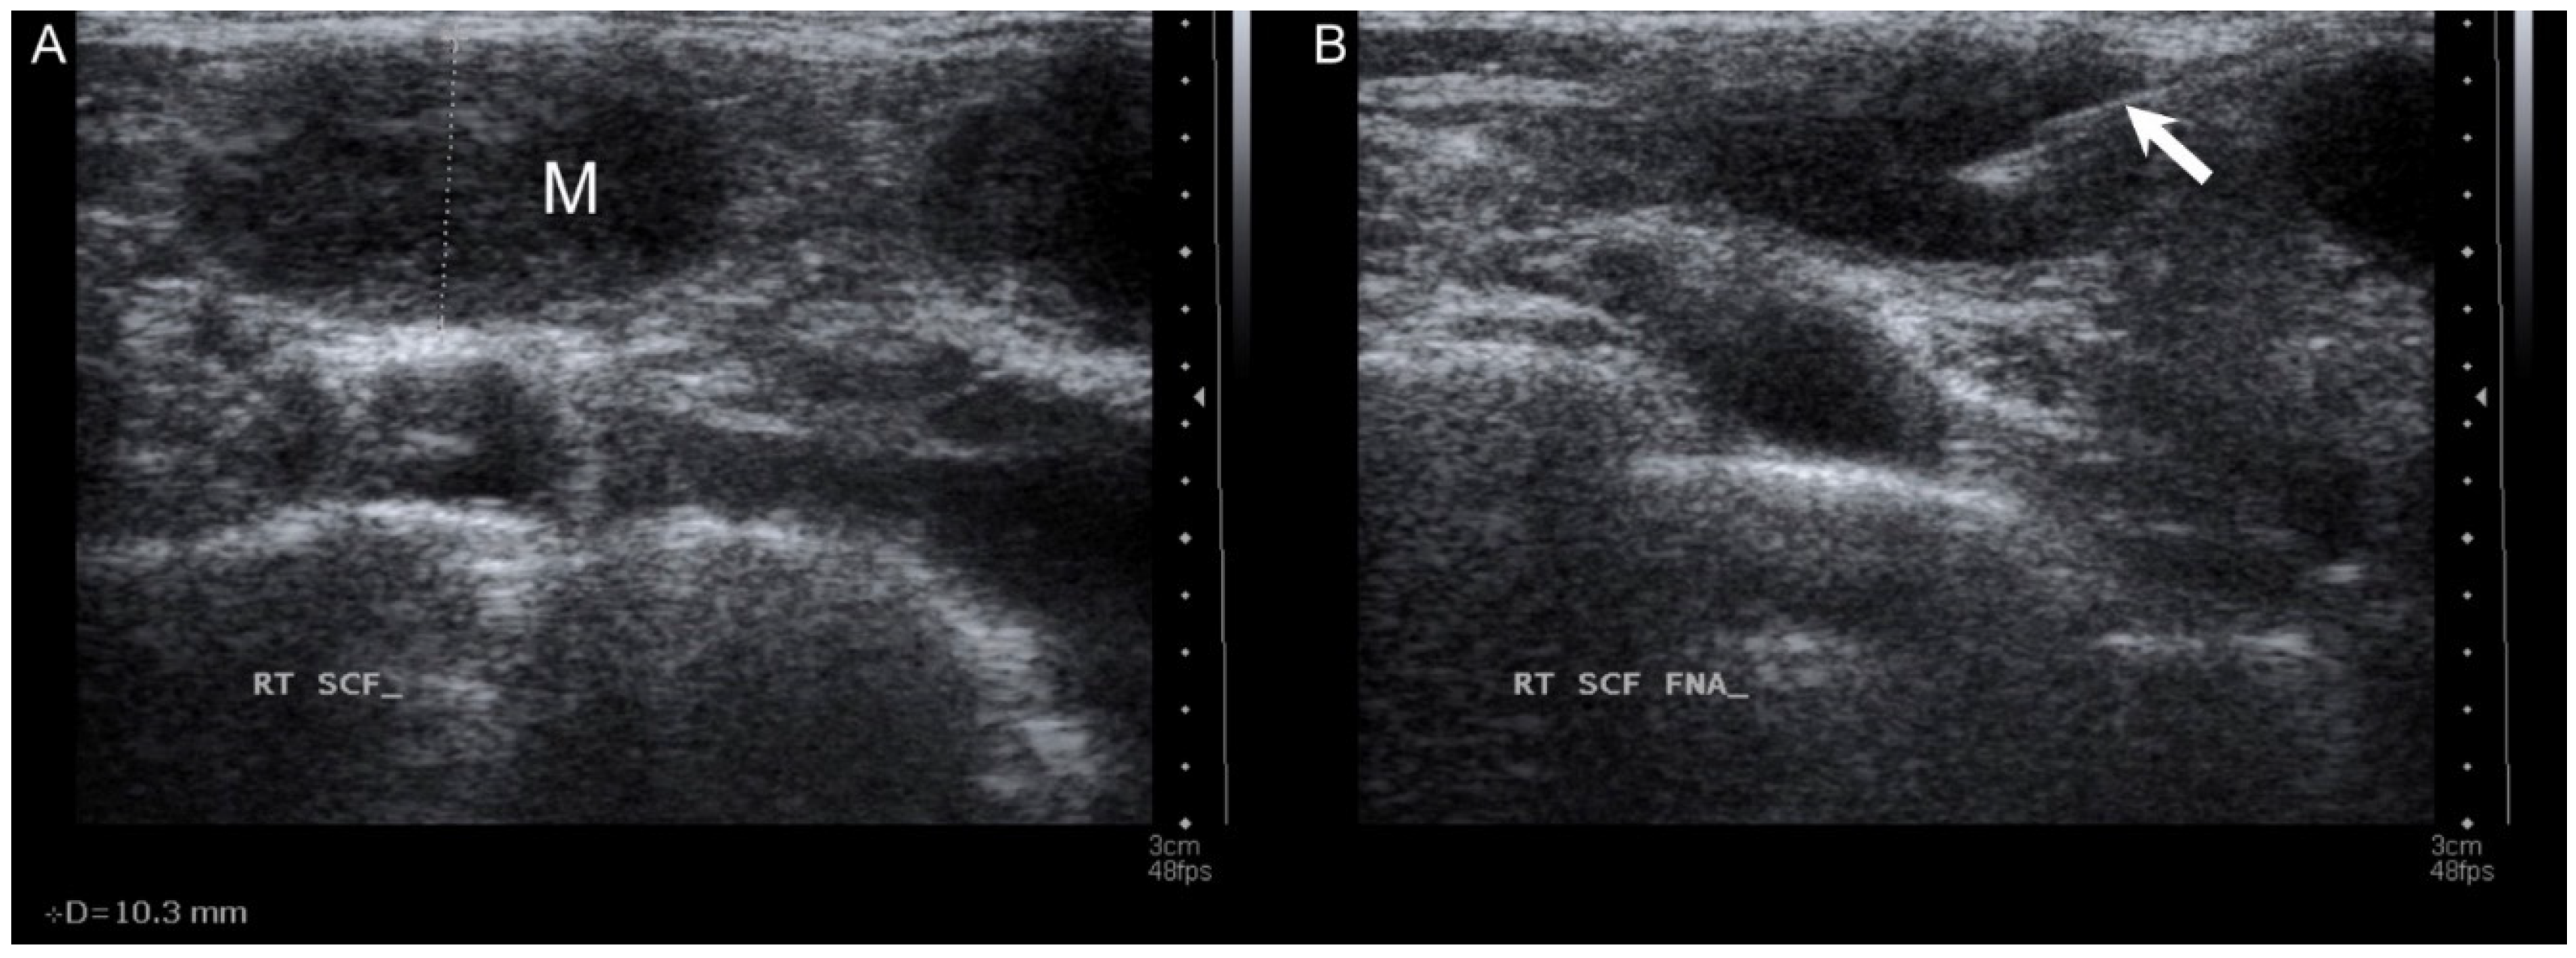

| Present case, 2021 | 53 | US, PET/CT | FNAC, excision | Serous adenocarcinoma | Low-grade | C | AWD, 2 |